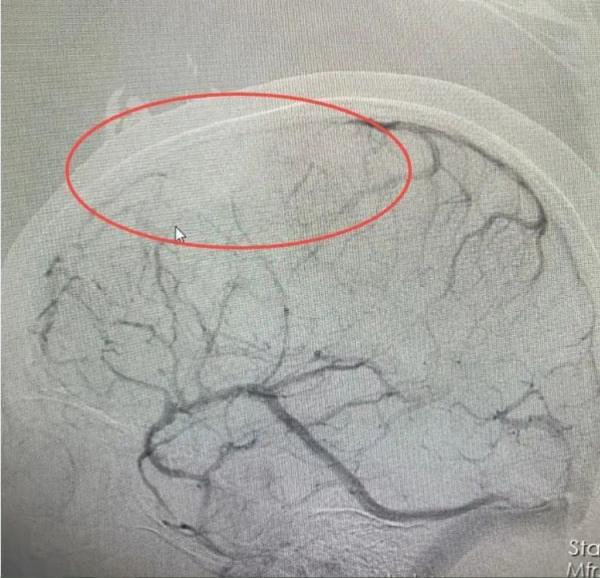

医院接诊医生仔细分析后,发现婷婷颅内病变不是脑肿瘤。结合病史和相关影像资料,该院神经内一科副主任匡祖颖初步怀疑是颅内静脉窦血栓,进一步完善全脑血管造影,证实是颅内静脉窦血栓形成合并出血 。